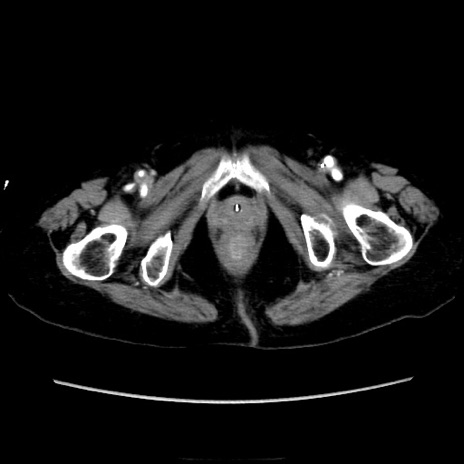

症例40(横断像)

横断像